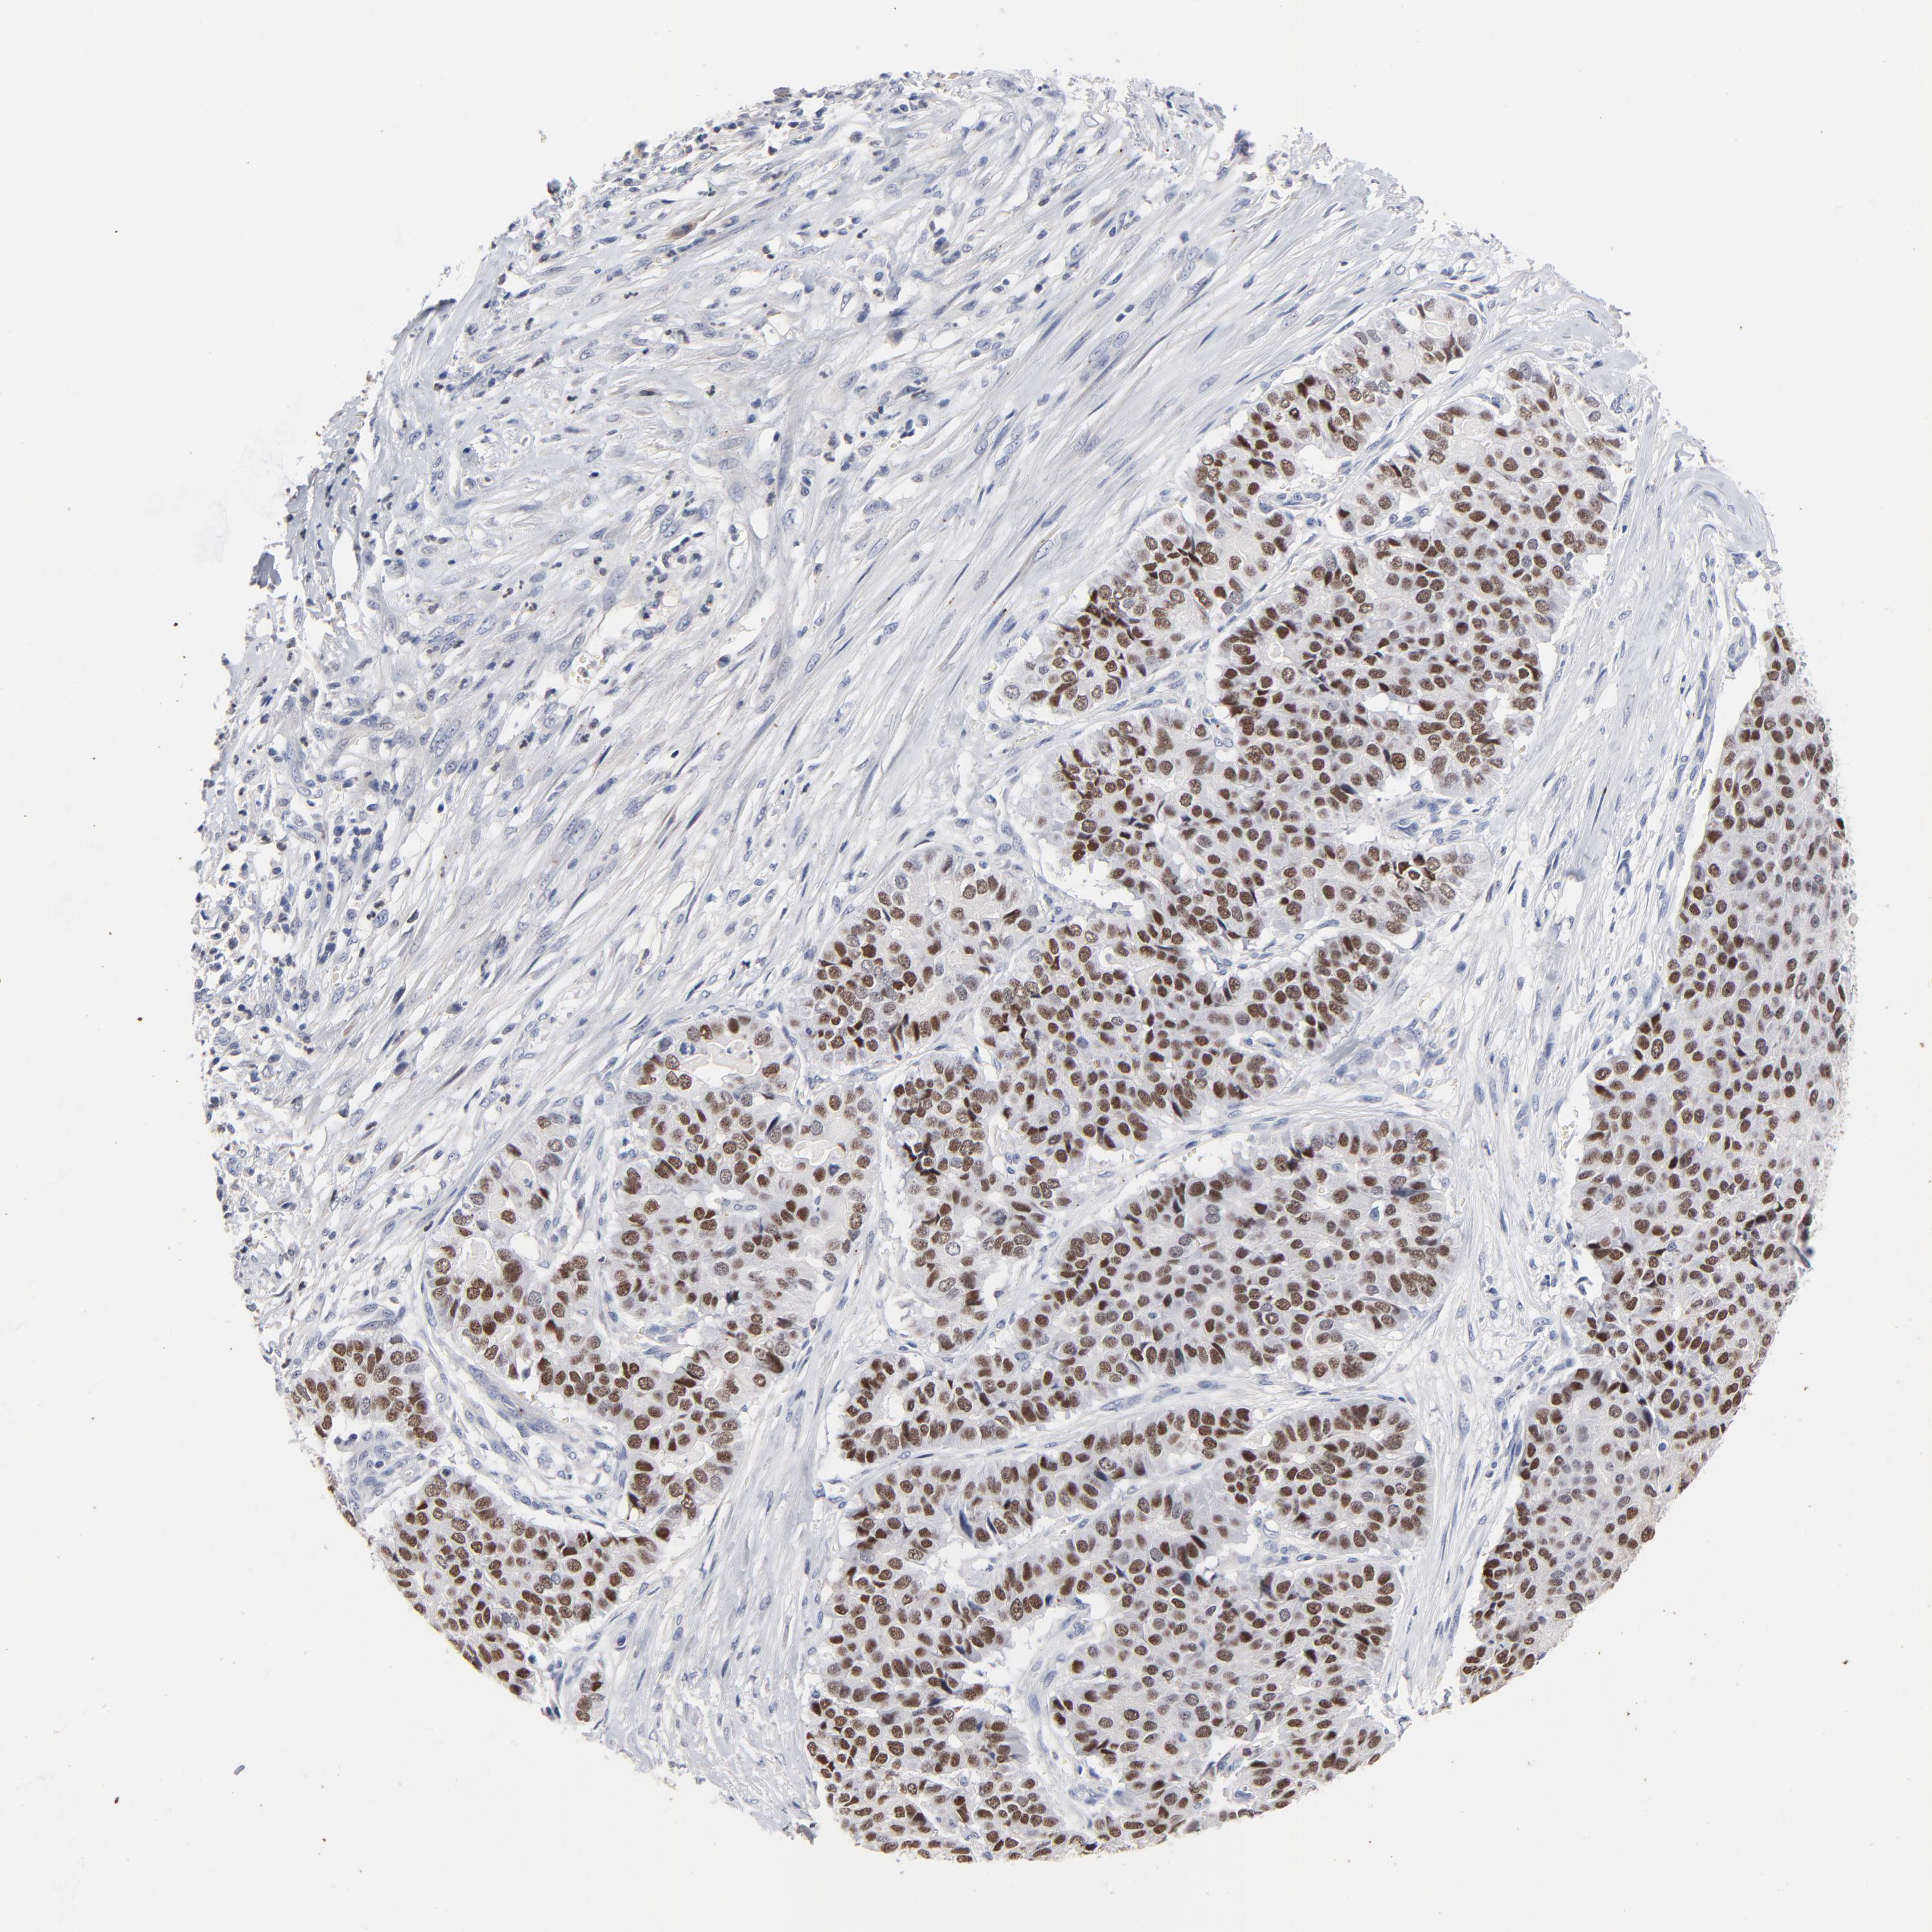

PANCREATIC CANCER - Protein expressioni

A mouse-over function shows sample information and annotation data. Click on an image to view it in a full screen mode. Samples can be filtered based on level of antibody staining by selecting one or several of the following categories: high, medium, low and not detected. The assay and annotation is described here.

Note that samples used for immunohistochemistry by the Human Protein Atlas do not correspond to samples in the TCGA dataset.

Antibody stainingi

Antibody staining in the annotated cell types in the current human tissue is reported as not detected, low, medium, or high, based on conventional immunohistochemistry profiling in selected tissues. This score is based on the combination of the staining intensity and fraction of stained cells.

Each image is clickable and will lead to virtual microscopy that enables deeper exploration of all samples and also displays staining intensity scores, fraction scores and subcellular localization as well as patient and tissue information for each sample.

Antibody HPA002911

Staining

High

Medium

Low

Not detected

Intensity

Strong

Moderate

Weak

Negative

Quantity

>75%

75%-25%

<25%

None

Location

Nuclear

Cytoplasmic/membranous

Cytoplasmic/membranous,nuclear

Adenocarcinoma, NOS

Adenocarcinoma, metastatic, NOS